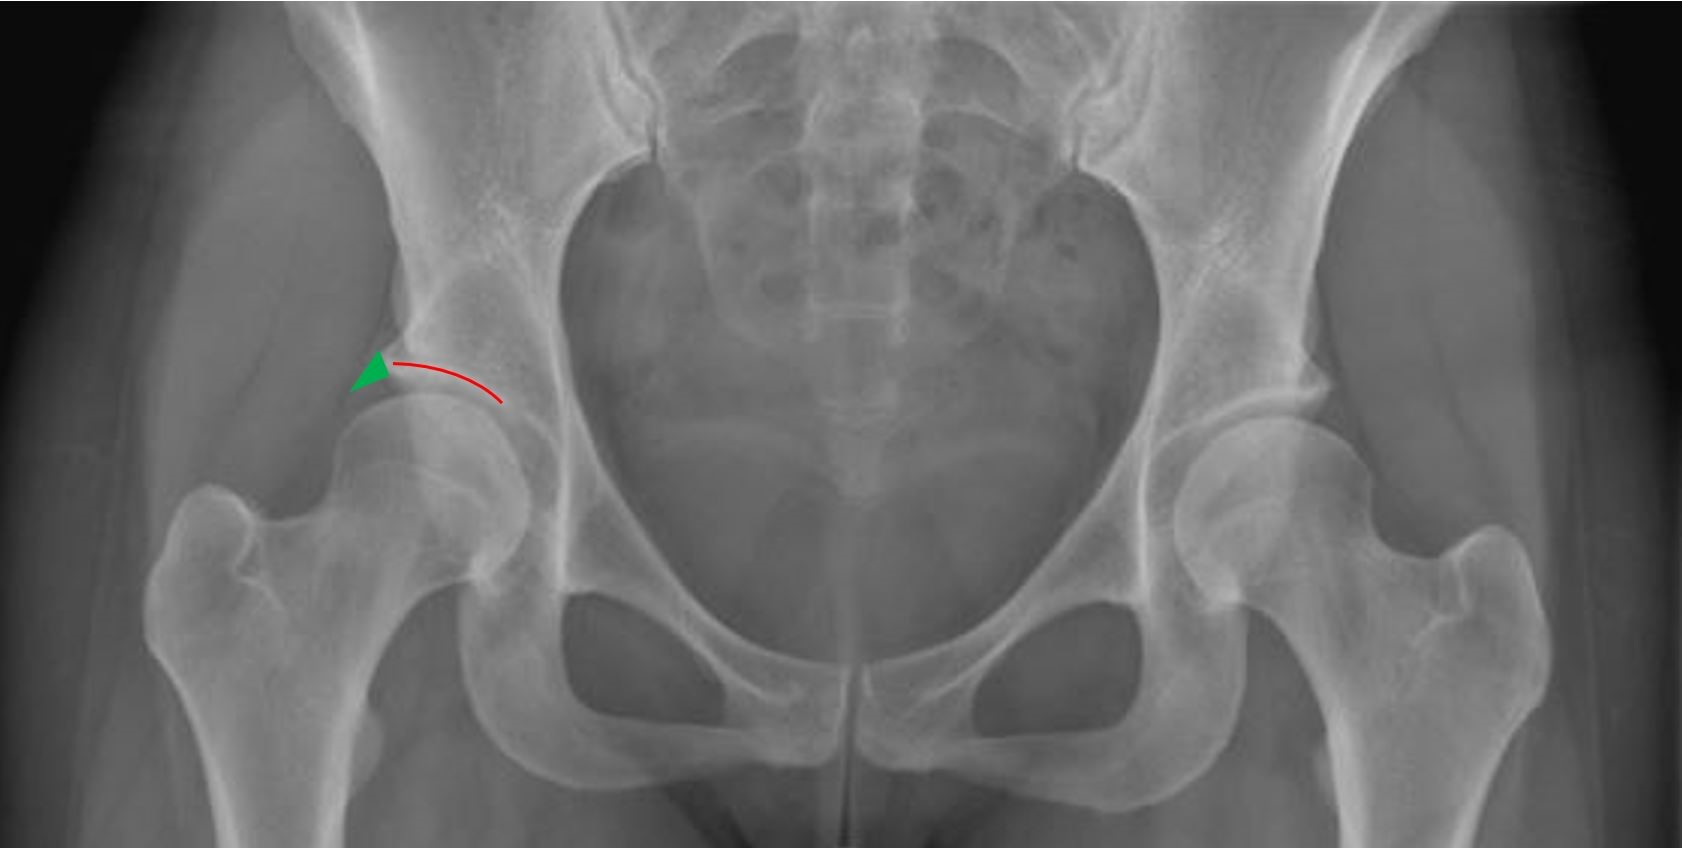

Im Röntgenbild zeigt sich eine zu kleine und steile Hüftpfanne mit zu geringer Überdachung des Hüftkopfes (siehe Röntgenbild unten). Eine Magnetresonanztomographie (MRT bzw. engl. MRI für magnetic resonance imaging) ist für die Diagnose nicht entscheidend, wird aber zur abschliessenden Beurteilung und Festlegung der Behandlung routinemässig durchgeführt.

Bild: Universitätsklinik Balgrist